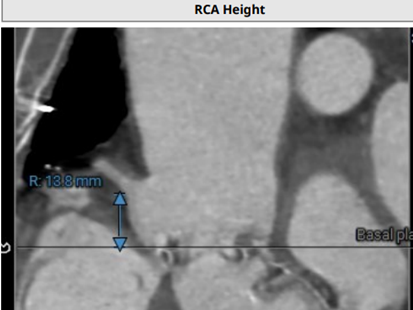

LCA开口高度:8.9mm,RCA开口高度:13.8mm: